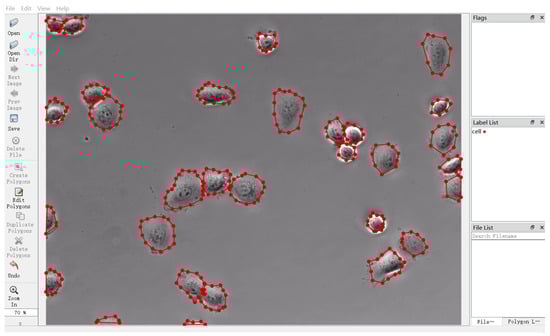

4.3. Data Annotation

- Russell, B.C.; Torralba, A.; Murphy, K.P.; Freeman, W.T. LabelMe: A database and web-based tool for image annotation. Int. J. Comput. Vis. 2008, 77, 157–173. [Google Scholar] [CrossRef]